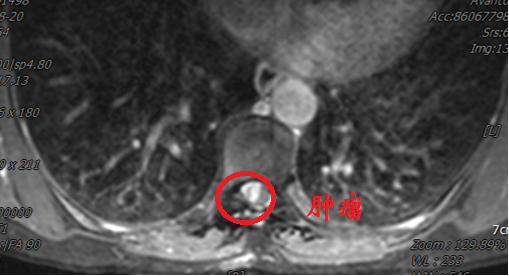

患者李女士(化名)来自西北少数民族地区,罹患胸段椎管内脊膜瘤,此前已在当地医院历经两次手术。近日,患她再次出现行走困难、疼痛难以平卧以及大小便费力,偶有失禁等症。患者首先回到最初就诊的省级医院,胸椎MRI示肿瘤再度复发,鉴于再次手术的难度和风险过高而被建议转院治疗。

几经辗转,患者来到西安交通大学第二附属医院神经外科就诊。郭振宇副主任医师接诊后,详细了解病情,发现“因多次手术,造成肿瘤与神经组织粘连严重,并且椎管腔内外解剖结构不清,再次手术患者瘫痪风险很高,并有可能大小便失禁”。